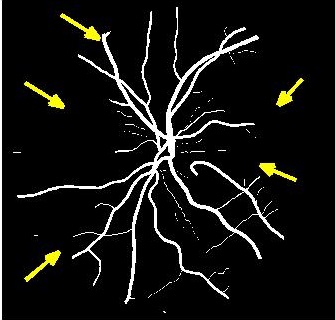

Figure 5 shows results of MA segmentation using the images generated by different super resolution methods. Figure 5 (a) shows the original full sized image with the regions having majority of the MAs outlined by a red square. Figure 5 (b) shows the cropped image region with yellow arrows identifying location of MAs. Figure 5 (c) shows manually drawn contours around the MAs. Figure 5 (d) shows the segmentation results obtained using the original HR images as part of the training and test set. The ground truth manual contours are shown in green while the segmentations obtained using the U-Net algorithm is shown in red. The performance on the HR images is an indication of the minimum error (or best possible segmentation performance). Figures 5 (e)-(h) show, respectively, the super resolved images obtained by , , and along with the super imposed segmentation results. It is quite obvious that the results obtained using are the best. It is interesting to note that the SR images obtained using and lead to blurred edges of the blood vessels and MAs, although in the case of the SR images are not blurred. The other two methods, and result in such poor quality images that the MAs are not even detected for this particular example.

Figure 4 (a) shows an example retinal image followed by its ground truth manual segmentation in Figure 4 (b). Figure 4 (c) shows segmentation result for scaling factor when using the original HR images to train the U-Net followed by the results when trained on the super resolved images generated by , (Figure 4 (d)), (Figure 4 (e)), (Figure 4 (f)), SR-RF (Figure 4 (g)), SSR (Figure 4 (h)) and (Figure 4 (i)). Obviously the results from provide results most similar to those of HR images. This is also validated by the quantitative results in Table 3. The areas where different methods are unable to obtain accurate segmentation are highlighted by yellow arrows. Due to poor quality of super resolved images most of the methods do not segment the finer vasculature structures, while SSR and SR-RF are unable to segment some of the major arteries. Importantly, our method performs much better than the low resolution image () which performs poorly due to low resolution.